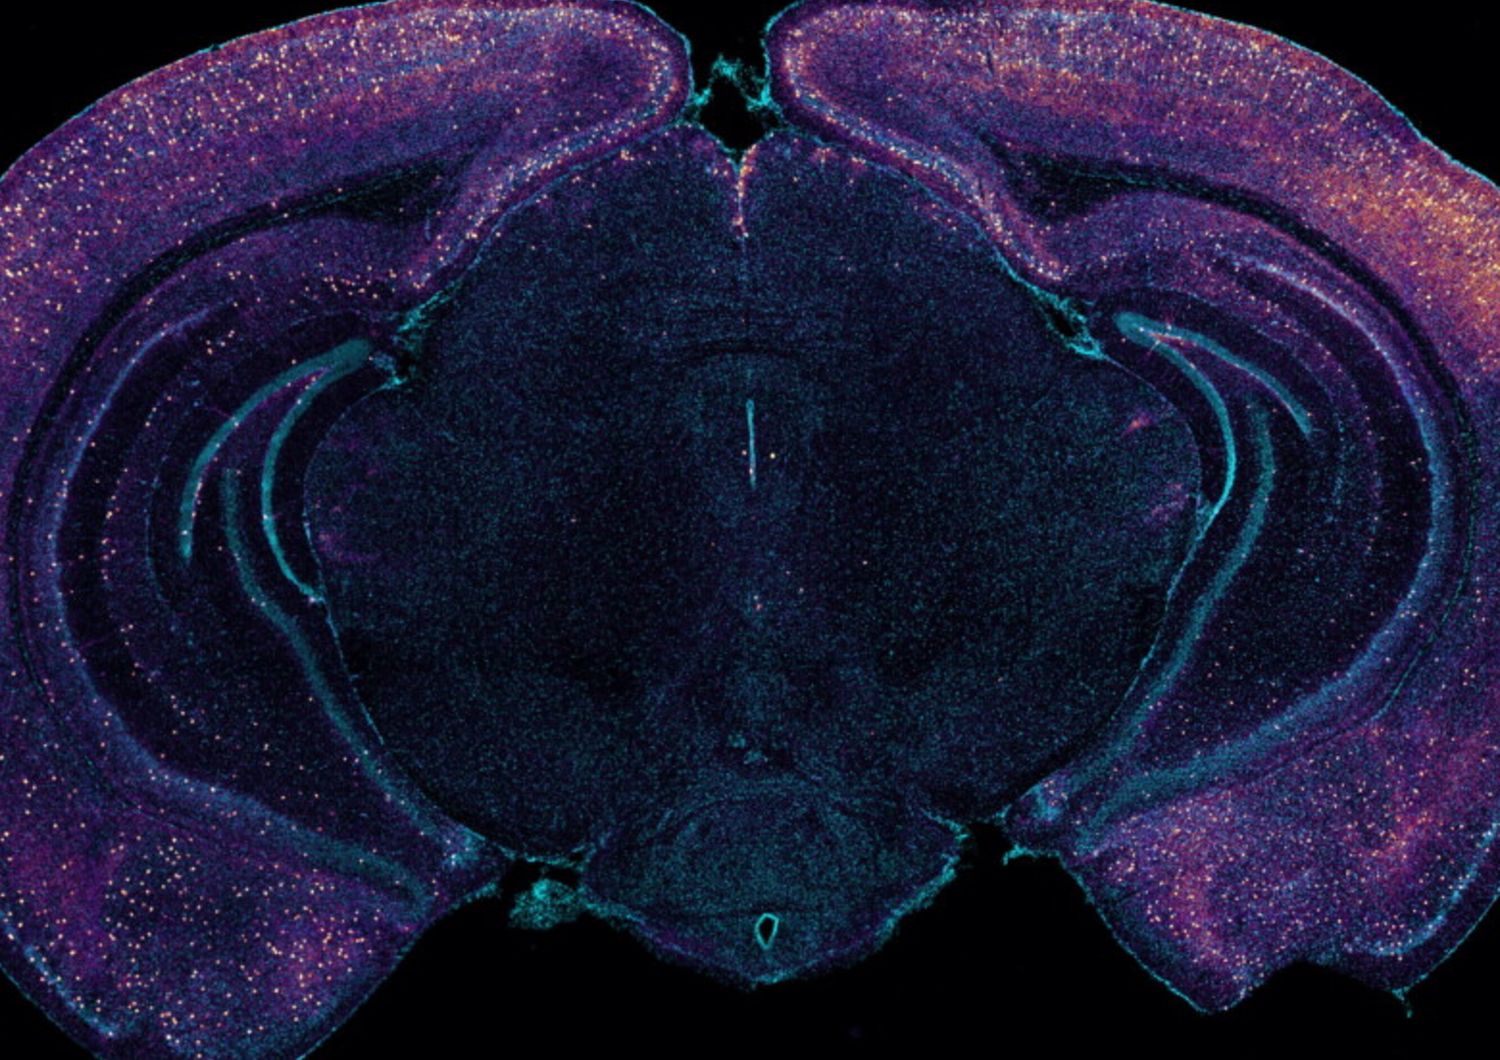

Lavorando con topi “5XFAD”, modello genetico dell’Alzheimer, Murdock e i coautori hanno replicato i risultati precedenti del laboratorio, secondo cui la stimolazione sensoriale a 40 Hz aumenta l’attività neuronale nel cervello e riduce i livelli di amiloide. Poi, hanno cercato di misurare se ci fosse un cambiamento correlato nei fluidi che scorrono attraverso il sistema glinfatico per rimuovere i rifiuti. In effetti, hanno misurato un aumento del liquido cerebrospinale nel tessuto cerebrale dei topi trattati con stimolazione sensoriale gamma, rispetto ai controlli non trattati. Gli scienziati hanno anche misurato un aumento della velocità di uscita del liquido interstiziale dal cervello. Inoltre, nei topi trattati con i raggi gamma è stato registrato un aumento del diametro dei vasi linfatici che drenano i fluidi e un maggiore accumulo di amiloide nei linfonodi cervicali, che sono il sito di drenaggio di questo flusso. Per capire le ragioni di questo aumento del flusso di fluidi, la squadra di ricercatori si è concentrata sul canale idrico dell’acquaporina 4, chiamato AQP4, delle cellule astrocitarie, che consente alle cellule di facilitare lo scambio di fluidi glinfatici. Bloccando la funzione dell’APQ4 con una sostanza chimica, si è impedito alla stimolazione sensoriale gamma di ridurre i livelli di amiloide e di migliorare l’apprendimento e la memoria dei topi. E quando, come ulteriore prova, gli scienziati hanno usato una tecnica genetica per interrompere l’AQP4, anche questa ha interferito con la clearance dell’amiloide guidata dai raggi gamma.

Oltre allo scambio di fluidi, promosso dall’attività dell’APQ4 negli astrociti, un altro meccanismo con cui le onde gamma promuovono il flusso glinfatico è l’aumento della pulsazione dei vasi sanguigni vicini. Diverse misurazioni hanno mostrato una maggiore pulsatilità arteriosa nei topi sottoposti a stimolazione sensoriale gamma rispetto ai controlli non trattati. Una delle migliori fra le nuove tecniche per tracciare il modo in cui una condizione, come la stimolazione sensoriale gamma, influisca su diversi tipi di cellule, è quella di sequenziare il loro RNA per seguire i cambiamenti nell’espressione genetica. Utilizzando questo metodo, la squadra di Tsai e Murdock ha osservato che la stimolazione sensoriale gamma promuoveva effettivamente cambiamenti coerenti con l’aumento dell’attività AQP4 degli astrociti. I dati di sequenziamento dell’RNA hanno, inoltre, rivelato che, in seguito alla stimolazione sensoriale gamma, un sottogruppo di neuroni, chiamati interneuroni, ha registrato un notevole aumento nella produzione di diversi peptidi. Ciò non sorprende, in quanto è noto che il rilascio di peptidi dipende dalle frequenze del ritmo cerebrale, ma è comunque degno di nota perché un peptide in particolare, il VIP, è associato a benefici contro l’Alzheimer e contribuisce alla regolazione delle cellule vascolari, del flusso sanguigno e della clearance glinfatica. Cogliendo questo intrigante risultato, il gruppo di scienziati ha eseguito dei test che hanno rivelato un aumento del VIP nel cervello dei topi trattati con i raggi gamma. I ricercatori hanno anche impiegato un sensore di rilascio di peptidi e hanno notato che la stimolazione sensoriale gamma determinava un aumento del rilascio di peptidi dagli interneuroni che esprimono il VIP. Infine, per scoprire se il rilascio di peptidi stimolato dai raggi gamma avesse mediato la clearance glinfatica dell’amiloide, la squadra di ricerca ha condotto un altro esperimento. Gli scienziati hanno prima spento chimicamente i neuroni VIP, poi hanno esposto i topi alla stimolazione sensoriale gamma, scoprendo che non vi era più alcun aumento della pulsatilità arteriosa e anche la clearance dell’amiloide, stimolata dai raggi gamma, non era più presente. “Pensiamo che siano coinvolti molti neuropeptidi”, ha commentato Murdock. “Una nuova importante direzione per la ricerca del laboratorio sarà quella di determinare quali altri peptidi o altri fattori molecolari possono essere guidati dalla stimolazione sensoriale gamma”, ha aggiunto Tsai. “Sebbene, questo lavoro si concentri su quello che probabilmente è un meccanismo importante, ovvero la clearance linfatica dell’amiloide, con cui la stimolazione sensoriale gamma aiuta il cervello, probabilmente non è l’unico processo di fondo che conta - hanno sottolineato Tsai e Murdock -. Gli effetti di eliminazione mostrati in questo studio si sono verificati piuttosto rapidamente, ma negli esperimenti di laboratorio e negli studi clinici sono state necessarie settimane o mesi di stimolazione sensoriale gamma cronica per avere effetti duraturi sulla cognizione”. Con ogni nuovo studio, tuttavia, gli scienziati imparano di più su come la stimolazione sensoriale dei ritmi cerebrali possa aiutare a trattare i disturbi neurologici.